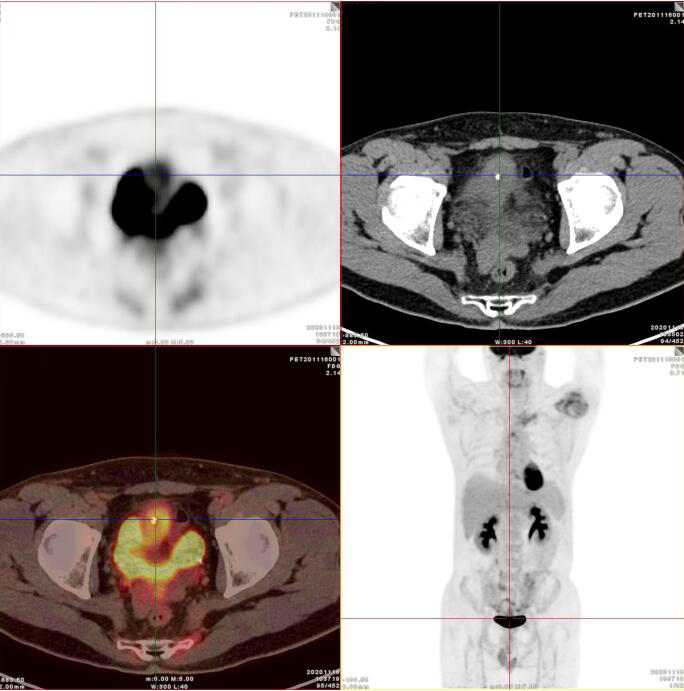

臍尿管擴(kuò)張,其管壁不均勻增厚,相應(yīng)區(qū)域膀胱頂前壁見一軟組織密度塊影,呈縱向生長,形態(tài)不規(guī)則,大小約3.3x3.8x6.3cm,內(nèi)見斑點(diǎn)鈣化!

膀胱頂前壁軟組織腫塊,放射性攝取SUV Max4.5

膀胱頂前壁軟組織腫塊,放射性攝取SUV Max4.5,延時(shí)4小時(shí)SUV Max8.3

臍尿管區(qū)及膀胱頂前壁軟組織腫塊,代謝增高,考慮臍尿管惡性腫瘤(臍尿管癌),建議穿刺活檢。